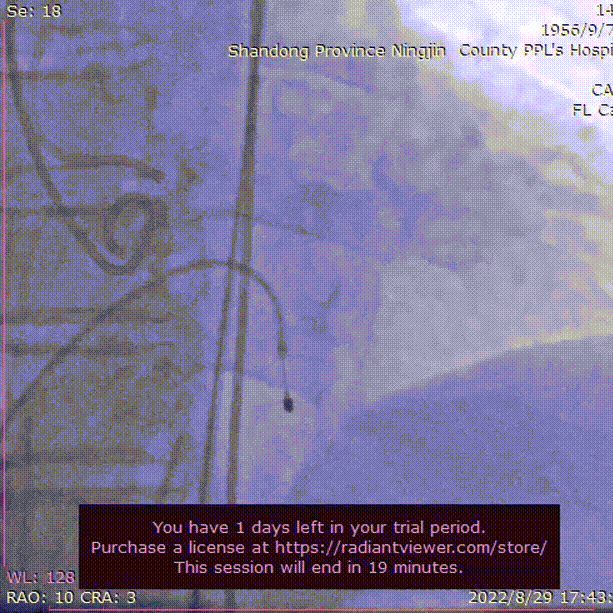

左股动脉切开,dsa引导下植入20Fr大鞘。行右侧猪尾导管主动脉根部造影、跨瓣。

外周造影

直头导丝跨瓣

20mm球囊预扩张,结合瓣环及术前策略,预装AV23型号瓣膜并释放至工作位。

球囊预扩

瓣膜释放至工作位

结合DSA影像,多角度观察瓣膜情况,瓣膜最终完全释放。

球囊后扩

造影评估

造影显示,因钙化原因,瓣膜贴合欠佳,行球囊后扩张,瓣膜形态佳,工作稳定,手术结束。